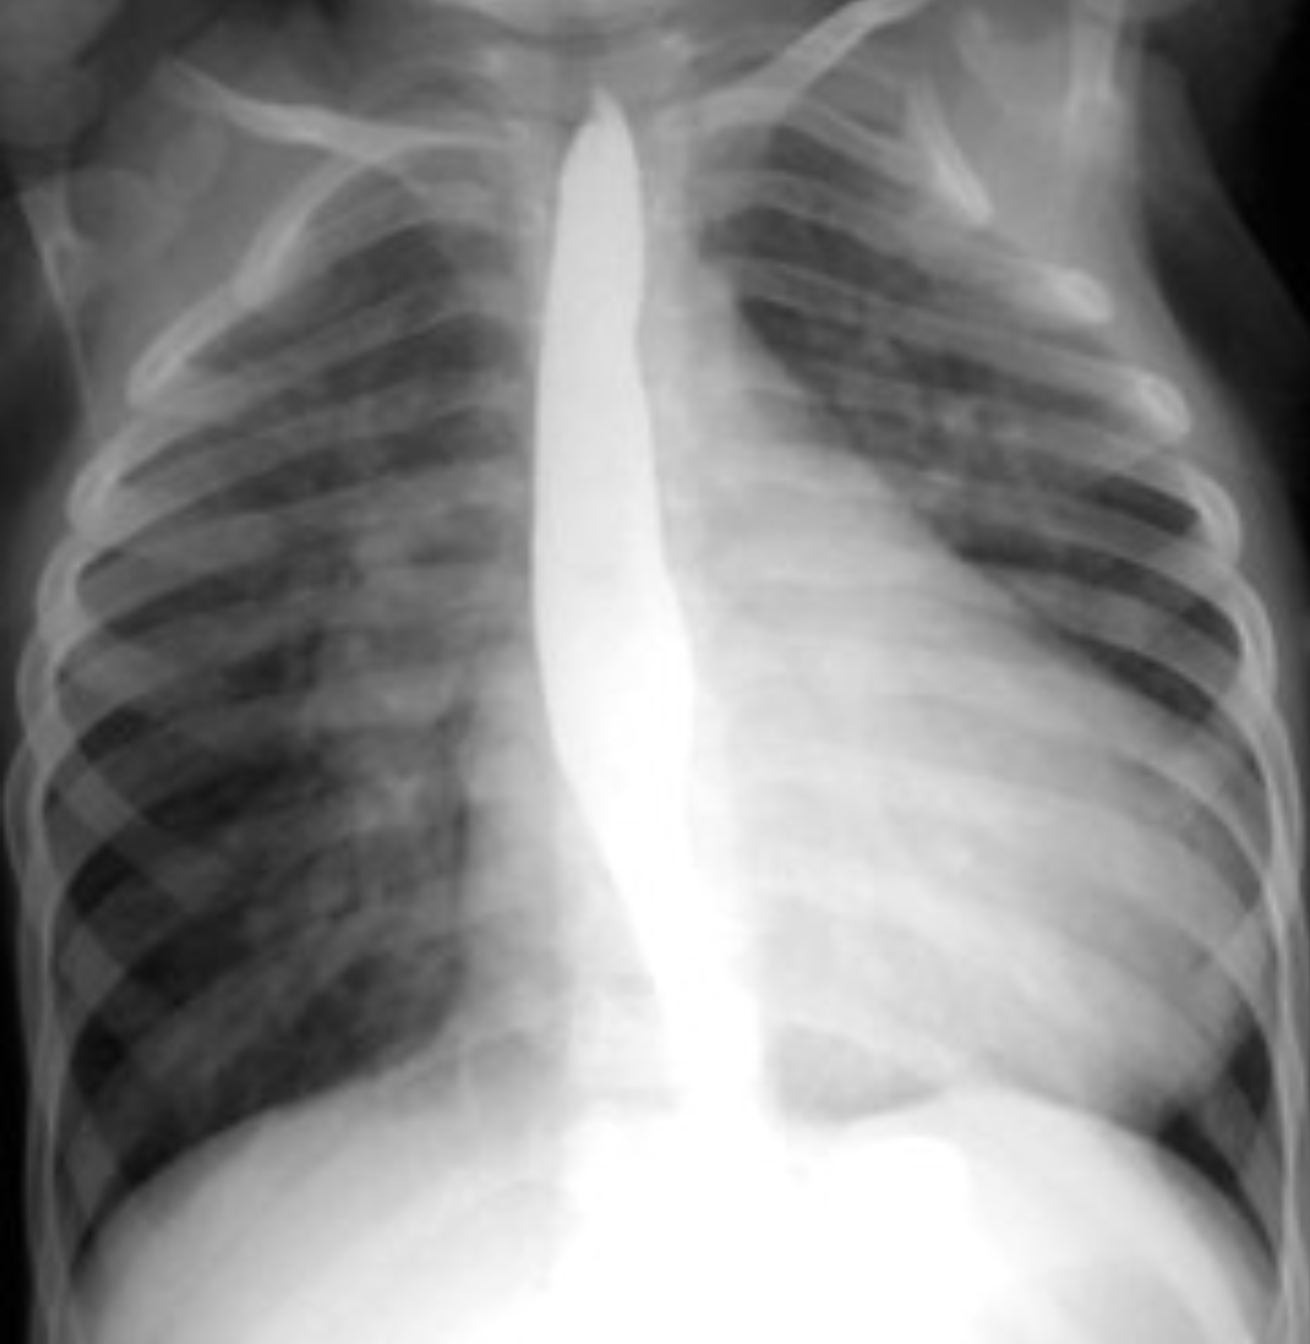

Stenoza aortica

- RGR:

- Hipertrofie Ventricul stang

- Adancirea golfului inimii

- Dilatatie de aorta ascendenta

- Aorta derulata +

-

- Al treilea arc pe dreapta

- MDCT, Eco: calcifieri valvulare, calcularea suprafetei orificiului valvular aortic, gradientii de presiune, fractia de ejectie, circulatia pulmonara, arterele coronare.

- IRM: jet poststenotic, morfologia si cinetica valvulara, hipertrofie VS, gradientii de presiune, fractia de ejectie

- Dilatatie de aorta ascendenta (al treilea arc pe dreapta)

- Hipertrofie Ventricul stang (initial minimal)

- Crosa aortica nu este afectata!